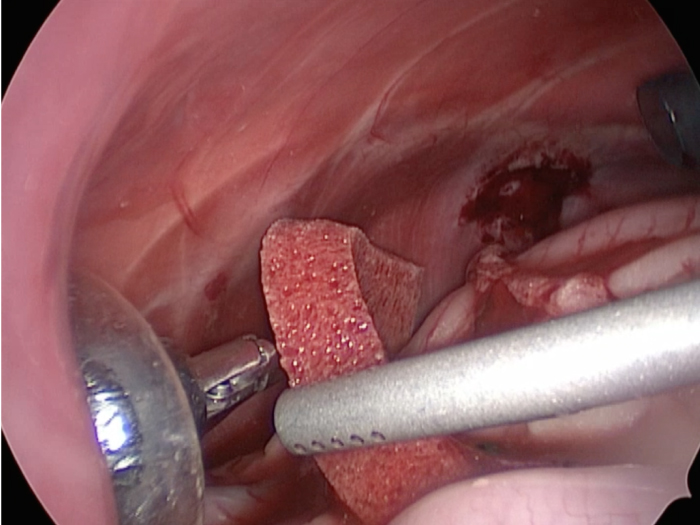

体の外に出すためお腹の中で袋に入れていきます。

このときに胆嚢と一緒にクリップやガーゼも回収します。

そしてお腹の中をきれいにしていきます。

最後にお腹の中をきれいに洗浄していきます。